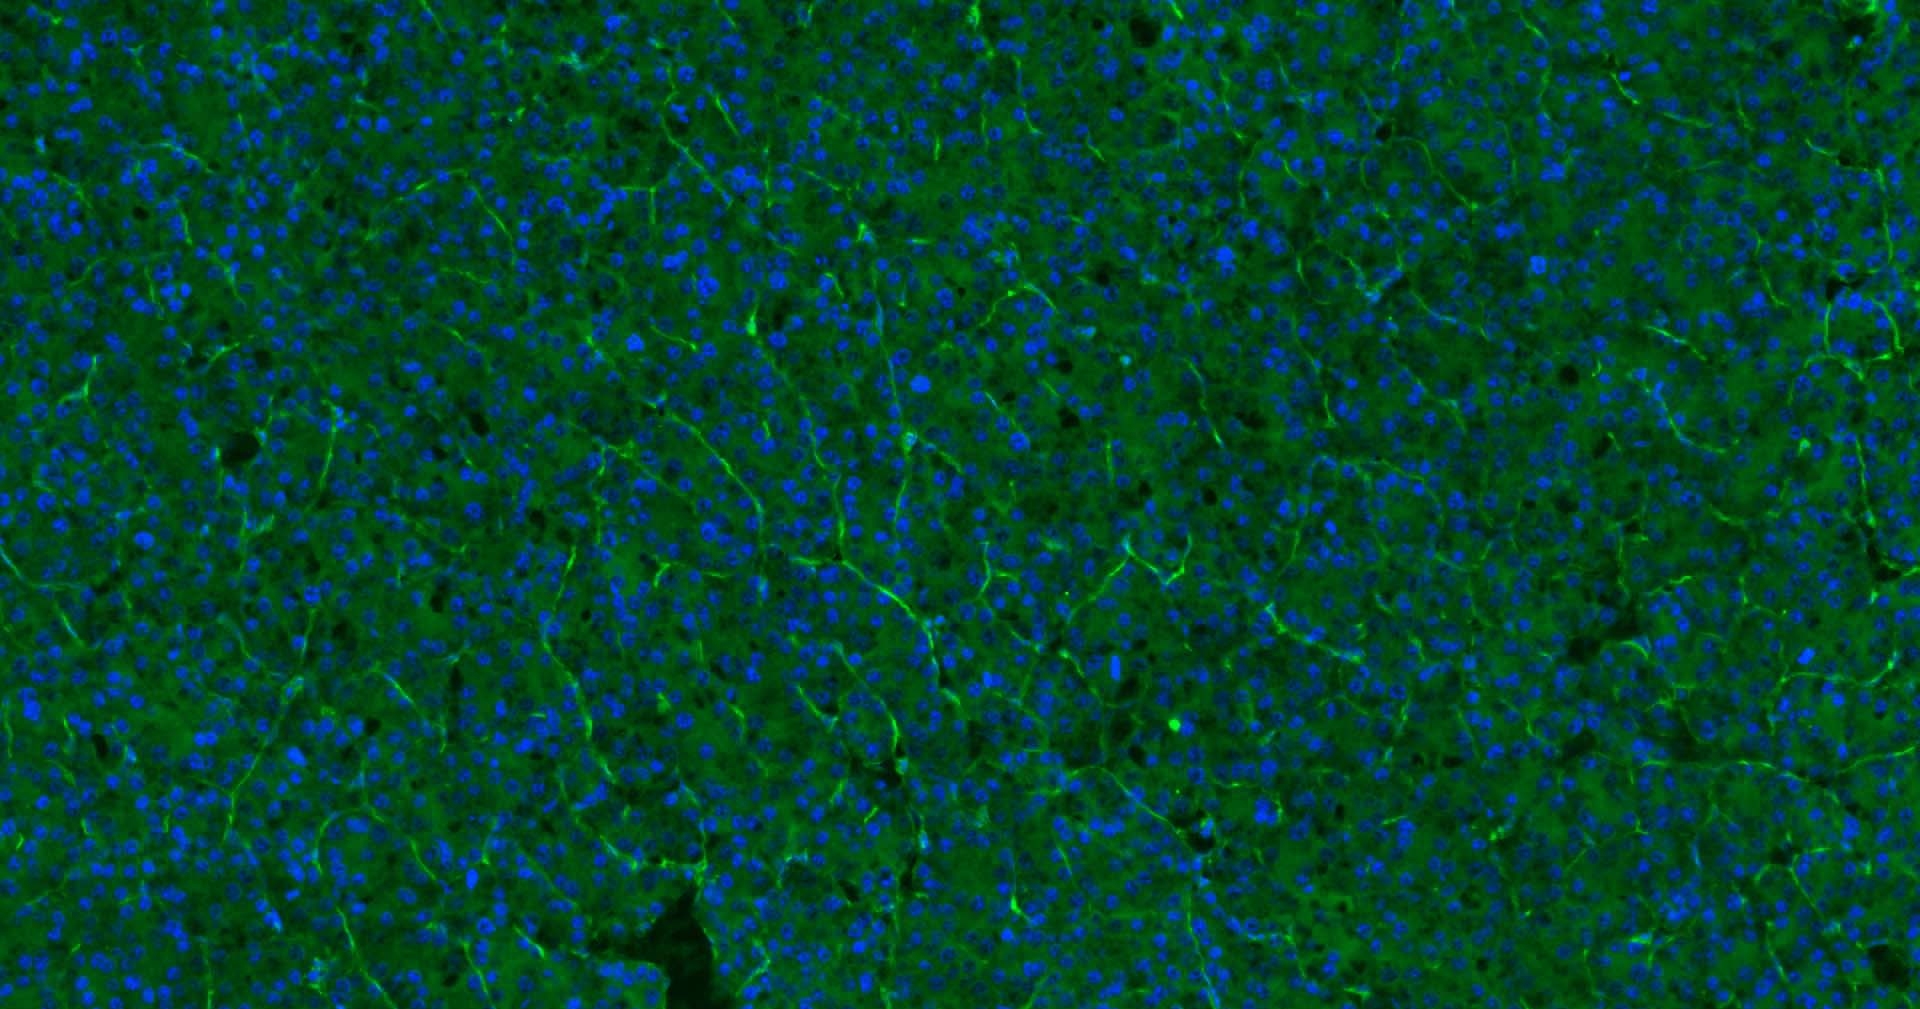

| IF | Human | 1:200-2000 | |

Expressed on platelets and leukocytes and is primarily concentrated at the borders between endothelial cells (PubMed:18388311, PubMed:21464369).

Expressed in human umbilical vein endothelial cells (HUVECs) (at protein level) (PubMed:19342684, PubMed:17580308).

Cell adhesion molecule which is required for leukocyte transendothelial migration (TEM) under most inflammatory conditions (PubMed:19342684, PubMed:17580308).